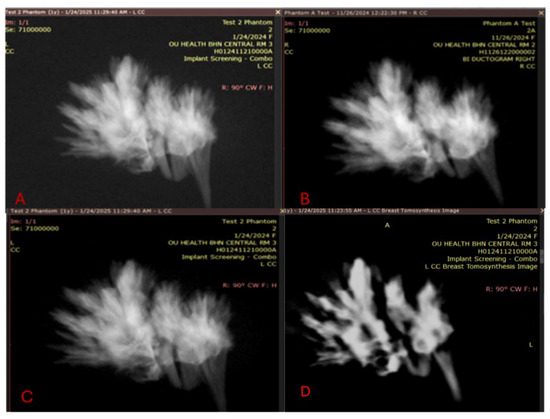

Quality visualization of the embedded crystals in the wax was performed and is shown in Figure 10, which reveals that the embedded crystals within the wax were clearly visualized in a comparison between a magnification view and a tomosynthesis reconstruction. These images were captured using a Selenia Dimensions scanner, magnification technique, and a single projected slice from the tomosynthesis.

Figure 10.

Magnification mode of our phantom image is shown on the left. The tomosynthesis image is shown on the right; the tomosynthesis image of the calcium carbonate embedded within the microcrystalline wax to model calcification in the breast was performed in a phantom and could be replicated on different machines during the development and evaluation of the systems.

Thus, the applications of these methods are either comparable to or exceed the baseline goals of the ACR QA phantom, particularly regarding the evaluation of calcifications. The physiological reasons for this are described in our Supplementary Materials. We achieved a strong visual similarity of the results across time, taking measurements ~2 months apart (26 November 2024 and 24 January 2025 measurements). All three measurements in the magnification scans were comparable and with a decrease in quality, as shown on the DBT images. Additionally, by taking two histogram evaluations in the area of calcification on two different scanners, we were able to observe the similarities between the measurements from Room 1 and Room 3, as revealed by comparing Figure 11 panels B and D with Figure 11 panels C and E. We performed tests on the normalized histogram data (Figure 11D,E). To quantitate, we performed a two-sample Kolmogorov–Smirnov test and demonstrated that these measurements appeared to be drawn from the same distribution (test statistic for KS two-sample test: D* = 0.0328 to 0.1389 for the comparison, which indicates that the samples came from the same distribution), with visualizations of the histograms from recent measurements taken on 24 January 2025 conducted in MATLAB R2023A, Natick MathWorks.

(A) Performed on 26 November 2024 in Room 2. (B) Repeat test performed on 24 January 2025 2 months later in Room 1. (C) In Room 3. (D) Tomosynthesis image taken from Room 3 on 24 November 2024. (E) Normalized histogram from Room 1. (F) Normalized histogram from Room 3.